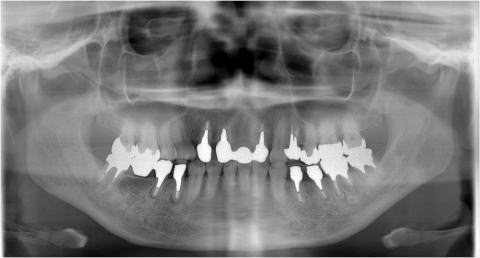

インプラント部分欠損症例

下顎両側臼歯部のインプラント治療

ケース1

下顎片側臼歯部のインプラント治療

ケース2